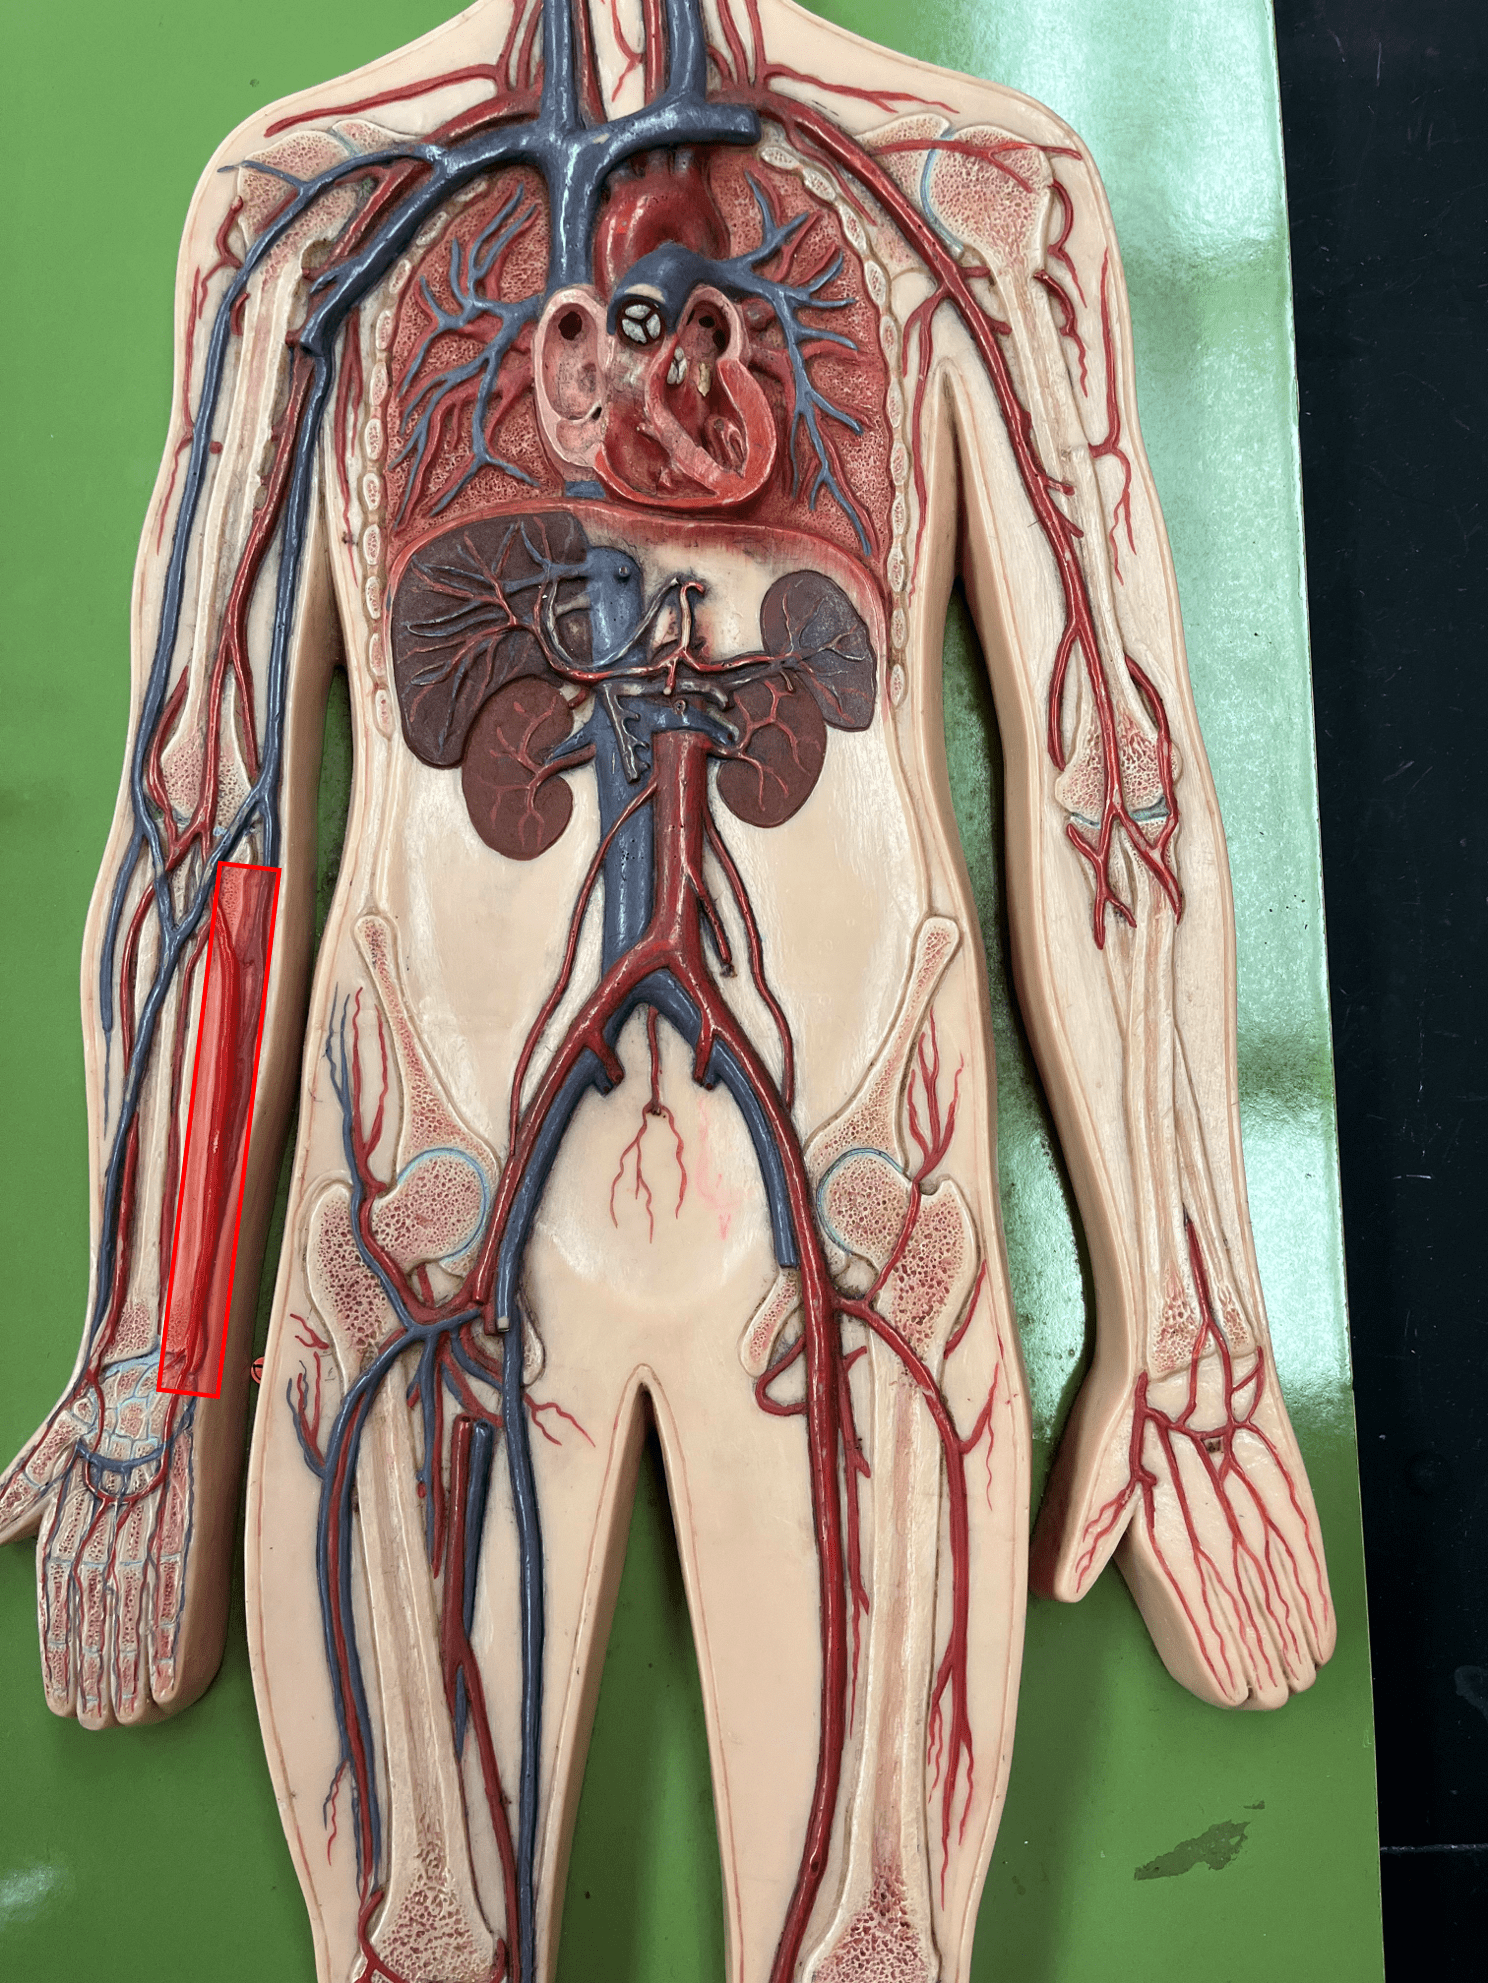

• Found between the tunica media and tunica interna.

• Allows the lumen of a blood vessel to stretch.

10

New cards

tunica interna

• The innermost layer of an artery.

• Consists of an inner endothelium and an outer basement membrane.

• Also known as the tunica intima.

• Consists of an inner endothelium and an outer basement membrane.

• Also known as the tunica intima.